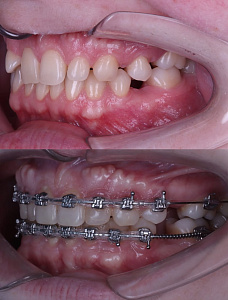

03.11.2025

Тохтиева Дана

Врач-ортодонт

repost be @d4anax end @orthodana.t

История одного ретенированного клыка. Мой первый максимально волнительный опыт с ретенцией. Лечение продлилось 2 года и 4 месяца. Были брекеты, винт, изгибы и другие, пружины, накладки, эластики, в общем - ВСЁ. Результат вышел красивый, на мой взгляд. Сейчас пациент уже готов без брекет-системы, ждем протезирования в области 12/22. По идее, дальше будет HOLLYWOOD SMILE, не иначе. Пациент счастлив, а я еще больше.

История одного ретенированного клыка. Мой первый максимально волнительный опыт с ретенцией. Лечение продлилось 2 года и 4 месяца. Были брекеты, винт, изгибы и другие, пружины, накладки, эластики, в общем - ВСЁ. Результат вышел красивый, на мой взгляд. Сейчас пациент уже готов без брекет-системы, ждем протезирования в области 12/22. По идее, дальше будет HOLLYWOOD SMILE, не иначе. Пациент счастлив, а я еще больше.